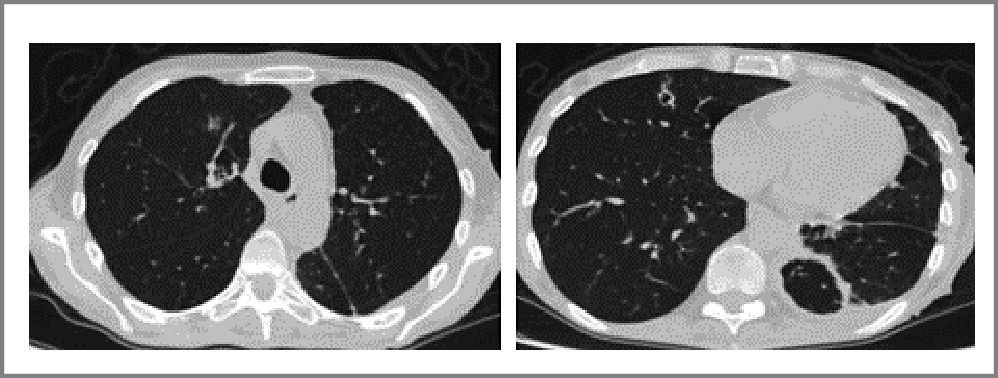

- Пациент М. 54 лет, в 2004 г. перенес экстренную илеоцекальную резекцию из-за кишечной непроходимости. Установлен диагноз БК в форме илеоколита, подтвержденный гистологически. В качестве противорецидивной терапии принимал азатиоприн. После исключения ТИ (ДСТ – отрицательный, РГ ОГК – без патологии) назначен цертолизумаба пэгол. Через 2 мес появилась лихорадка до 39°С, потливость, выраженная общая слабость, непродуктивный кашель. По данным КТ в легких выявлены множественные очаги 1–2 мм, лимфаденопатия средостения; множественные очаги в селезенке от 3 до 19 мм, слабо накапливающие контраст. Анализ крови: лейкоцитоз 13,2×109/л, скорость оседания эритроцитов 86 мм/ч, С-реактивный белок 292 мг/л. Мазок на SARS-CoV-2 – отрицательный. При эзофагогастродуоденоскопии и колоноилеоскопии данных за рецидив БК не получено. Полимеразная цепная реакция (ПЦР) биоптата слизистой оболочки толстой кишки: ДНК Mycobacterium tuberculosis не обнаружена. Терапия антибиотиками широкого спектра оказалась не эффективной. При КТ отрицательная динамика: увеличение количества и размеров очаговых поражений в легких и селезенке до 15 мм, лимфоузлы представлены конгломератами до 25 мм (рис. 1).

Рис. 1. КТ ОГК. Диссеминированный ТБ легких у пациента М. Многочисленные мелкие очаги в легких, увеличенные медиастинальные лимфатические узлы.

Fig. 1. CT scan of thoracic organs: Disseminated pulmonary tuberculosis in patient M. Numerous small lesions in the lungs, increased mediastinal lymph nodes.

Повторный ДСТ – положительный (гиперемия 10 мм). Выполнен T-Spot.TB – результат положительный. Установлен диагноз «гематогенно-диссеминированный ТБ». Пациент переведен в ГБУЗ «МНПЦ борьбы с туберкулезом», где проведена противотуберкулезная терапия. Вышеописанные симптомы регрессировали. При госпитализации в отделение патологии кишечника ГБУЗ «МКНЦ имени А.С. Логинова» в декабре 2022 г. данных за рецидив БК не получено. Пациенту назначен ведолизумаб в качестве поддерживающей противорецидивной терапии БК.